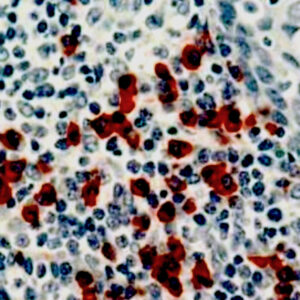

Anti-Cytokeratin 14

Keratins are intermediate filament proteins expressed by epithelial cells in cytoplasm. Mitotically active basal layers of most stratified squamous epithelia cells express 10% to 30% of their total protein as keratin. Cytokeratin 14 (CK14) is a 50-kDa keratin expressed in abundance in epidermal cells, basal cells, mesothelial cells, stratified epithelial cells, and myoepithelial cells in various tissues including prostate and breast. CK14 is helpful in the identification of breast cancer with basal phenotype